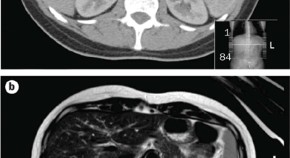

• This article presents the case of a child with pseudohypoparathyroidism type 1a and associated endocrinopathies, namely, growth hormone deficiency, hypothyroidism, parathyroid hormone resistance and insulin resistance. The article details the natural history and management of these endocrinopathies, including the controversy over growth-hormone therapy, and potential mechanisms for insulin resistance in pseudohypoparathyroidism type 1a.

• Benjamin U. Nwosu

• Mary M. Lee